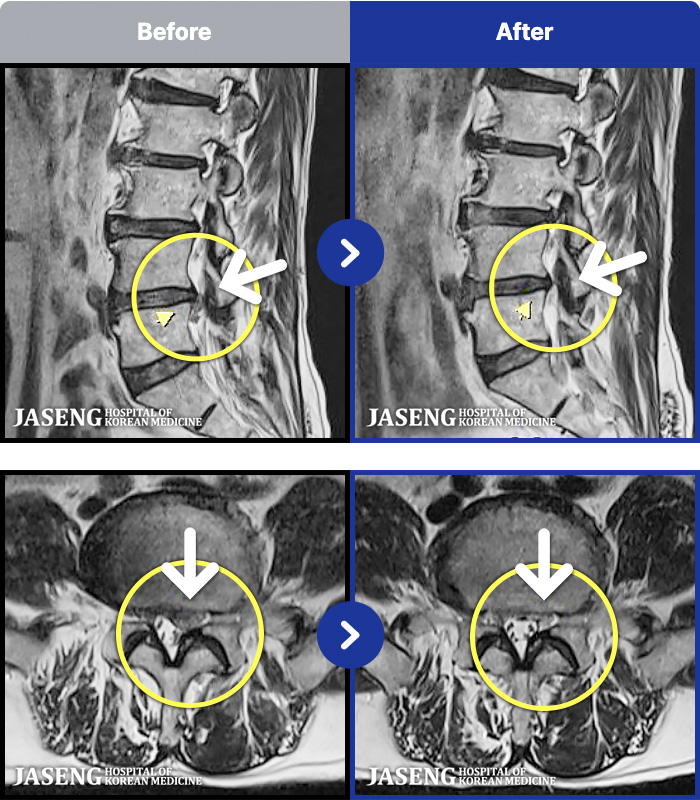

1,297 MRI ũ ʸ Ȯϼ.

[] 23.11.11~25.06.04